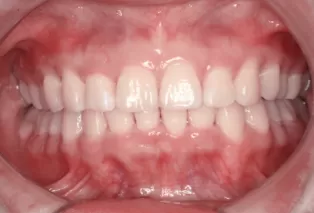

Female, 25 years old. Chief complaint: protruding and misaligned teeth, requiring orthodontic treatment.

Intraoral photos

Intraoral photos after treatment